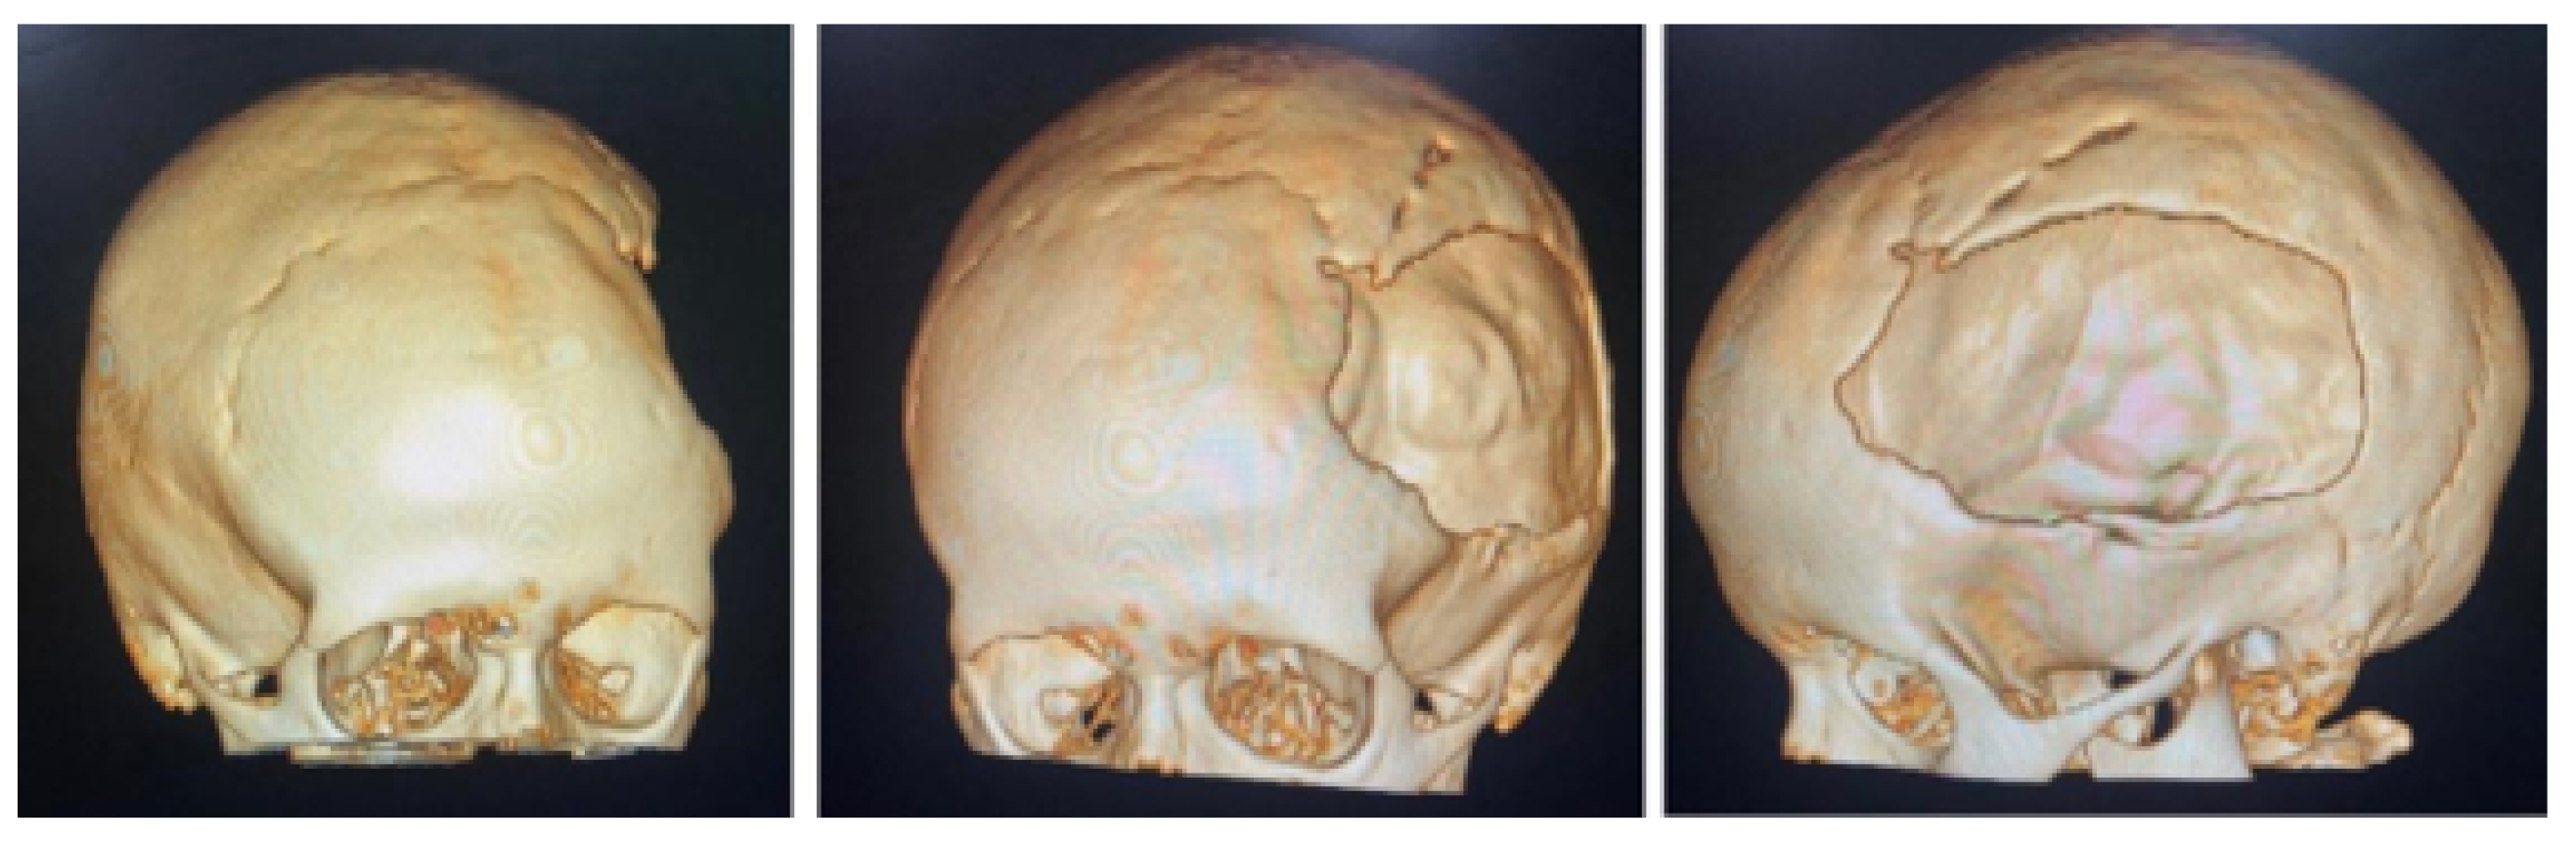

3.1. Case 1: Skull Trauma Sequel

3.1.1. Diagnosis and Analysis

3.1.2. Surgical Planning

3.1.3. Planning and Printing Anatomical Model